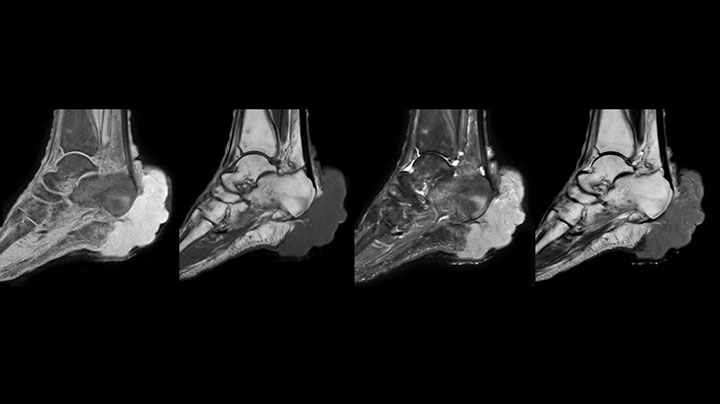

Clinical cases from Seirei Mikatahara General Hospital

mDIXON TSE of ankle

MRI examination on Prodiva 1.5T of a 72-year-old female with a malignant melanoma in the ankle. mDIXON TSE provides excellent fat suppression, without the distortion that is often seen at such extremities.